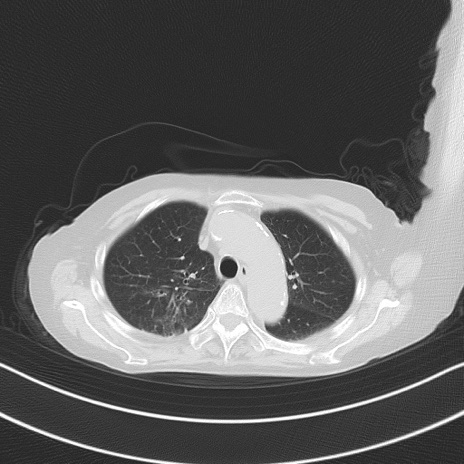

横断像

他院CT